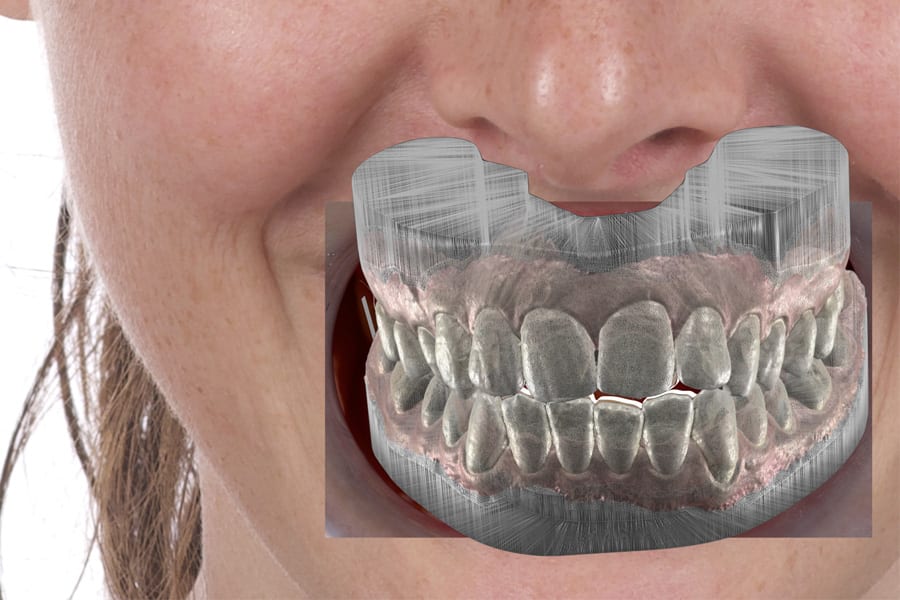

Digital Workflow: From 2D Smile Design to 3D Orthodontic Setup

Digital smile design (generic software) is used to align facial objectives with tooth position, communicate across the team, and provide a stepwise roadmap for orthodontic staging and intrusion targets. It also allows for visualization of consequences of “close-in-front” versus posterior intrusion strategies in high-display cases.6-8 (Figure 7 through Figure 9)